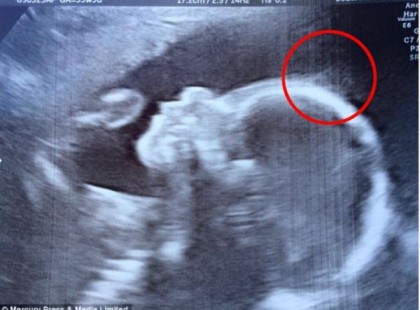

Az orvosok megrökönyödnek, amikor az ultrahangon valami furát vesznek észre a kicsi fején: Így néz ki napjainkban a kisbaba!